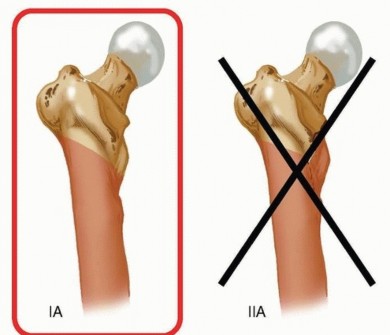

Table 1 Relative Indications for Retrograde Intramedullary Nailing of the Femur Indication Rationale All femoral shaft fractures Shown in multiple studies to have equivalent union rates and outcomes to antegrade intramedullary nailing Pregnancy Ability to decrease the amount of radiation exposure to the fetus Bilateral femur fractures Decreased overall operative time because the lower extremities can be prepared and draped together, eliminating the need to reposition for the second procedure Floating knee injuries Single surgical approach Polytrauma patient Supine positioning without bump allows for multiple surgical team approach to patient. Unstable spine injuries Supine positioning without bump affords ability to maintain spine precautions throughout the procedure. Acetabular or pelvic fractures Avoids surgical incision about the hip that may limit future surgical approaches Ipsilateral hip and femoral shaft fractures Allows each fracture to be treated with the optimal implant Ipsilateral femoral shaft fracture below a total hip replacement stem Short supracondylar retrograde nails can be used to treat the fracture with a minimally invasive technique. Morbid obesity Easier and more limited surgical approach Soft tissue wounds about the hip Avoids surgical approach of compromised soft tissues Retrograde femoral nailing is not considered to be the standard of care for treatment of more proximal subtrochanteric fractures, but in certain patient circumstances, it may be the treatment of choice ( Table 1). Subtrochanteric fractures with the lesser trochanter and piriformis fossa intact, Russell-Taylor IA fractures ( FIG 4),25 may be amenable to retrograde femoral nailing if other patient factors favor a retrograde approach. Ideally, some proximal medial cortex remains intact to act as a buttress against the nail. It is important to know how far the proximal interlocking screw holes are from the tip of the nail in the retrograde nail system available in your hospital. We recommend being able to obtain two bicortical interlocking screws above the most proximal fracture line for very proximal fractures. If possible, they should be through holes, not slots, in the nail to provide more stability. If the subtrochanteric fracture has proximal extension, including either the lesser trochanter or piriformis fossa, or both, then proximal interlocking screw fixation of the retrograde nail would be compromised and alternative fracture fixation methods should be considered. Retrograde femoral nailing may be considered in certain supracondylar distal femoral fractures. We find that Muller's AO classification system of distal femoral fractures 16 best elucidates which of these fractures can be addressed with retrograde femoral nailing ( FIG 5). Consideration for retrograde femoral nailing can be given for all extra-articular (A subgroup) fractures. It is important to know the distance between the distal interlocking screw holes and the tip of the nail in the retrograde nail system available in your hospital. We recommend being able to obtain at least two bicortical interlocking screws below the most distal fracture line for distal fractures. Nails with oblique distal interlocking options can be advantageous because of increased stability and potentially less screw head prominence.  ---

---  ### FIG 4 • Russell-Taylor classification system of subtrochanteric femur fractures,25 with fracture patterns amenable to retrograde femoral nailing highlighted.

### FIG 4 • Russell-Taylor classification system of subtrochanteric femur fractures,25 with fracture patterns amenable to retrograde femoral nailing highlighted.